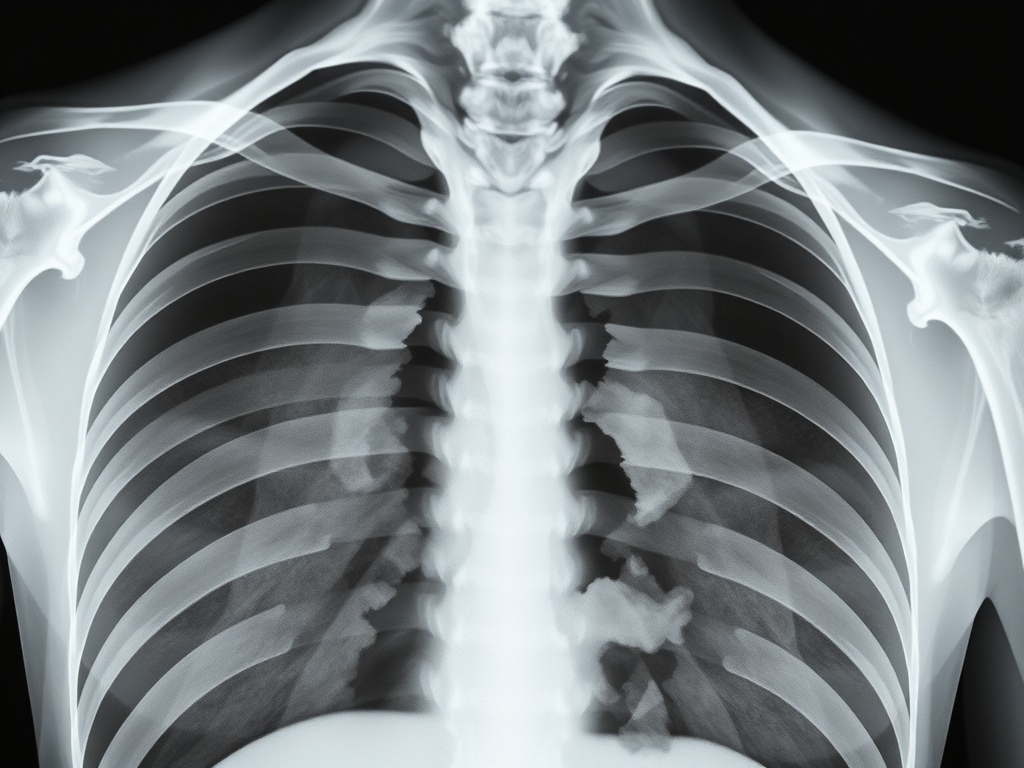

- ๊ณจ์ ๋ชจ๋ํฐ๋ง: ์ ๊ธฐ์ ์ธ X-ray ๊ฒ์ฌ๋ฅผ ํตํด ๊ณจ์ ์ ํ๋ณต ์ํ๋ฅผ ํ์ธํด์ผ ํฉ๋๋ค.